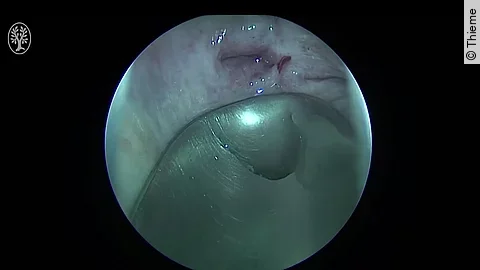

Cystoskopie, DJ-Entfernung (27.04.2023)

• 27.04.2023

• 00:11:48